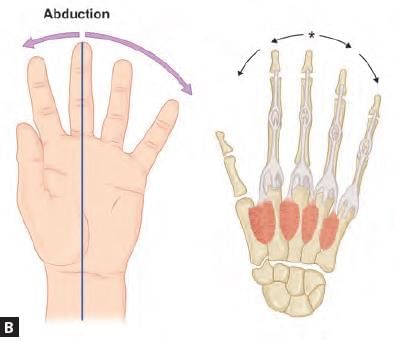

Which of the following finger has two dorsal interossei? (AIIMS May 2019)

Which of the structure does not contribute to the pointed structure? (AIIMS Nov 2019)